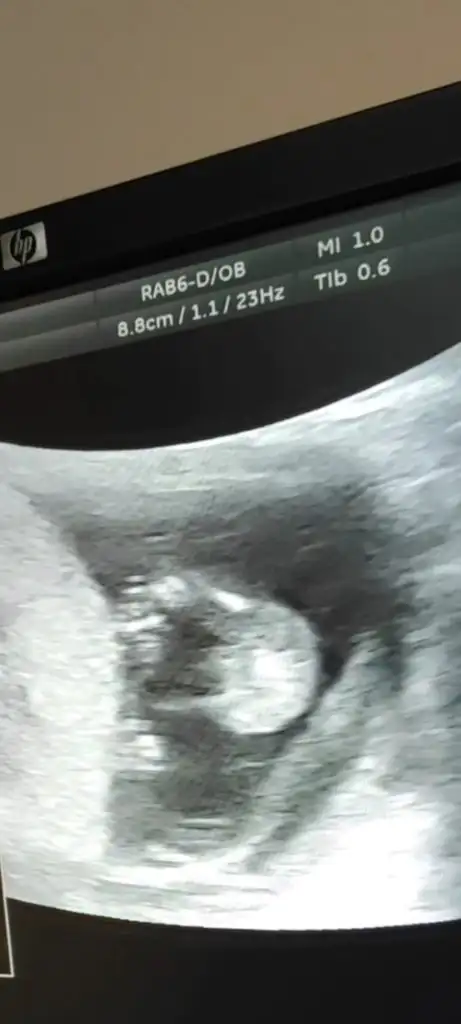

11 hafta olduk bakrmsnTabii atın bakayım, isterseniz buradan isterseniz özelden atın fark etmez

Banada yorum yaparsanız çok sevinirimErkeğe benzettim, ama 10 ile 14 hafta arası tekrar atın

Benimkine de bakabilir misiniz doktorum 11+5te kız dedi 13+6da erkek dediUltrason resmi varsa 11 ile 13 arası nub belli ise bizde tahminde bulunabiliriz

Atsam bakarmısınızUltrason resmi varsa 11 ile 13 arası nub belli ise bizde tahminde bulunabiliriz

1 i hariç hepsi kız gibi %75 kız derdimAtsam bakarmısınız

%80 kız gibi duruyor. Hayırlısı olsun inşallahBenimkine de bakabilir misiniz doktorum 11+5te kız dedi 13+6da erkek dedi